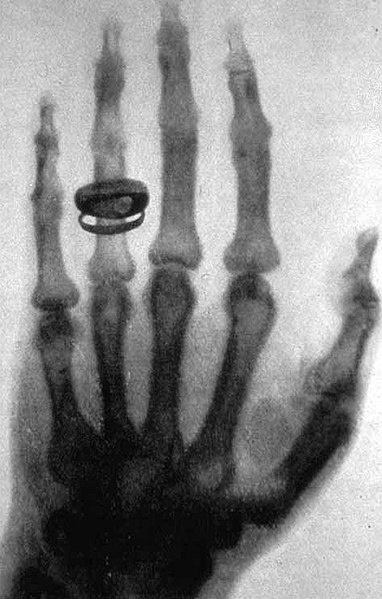

Image of an early X-ray: X-ray of a left hand taken at a public lecture by Wilhelm Röntgen

Image: “An early X-ray” by Wilhelm Röntgen; current version created by Old Moonraker. License: Public Domain